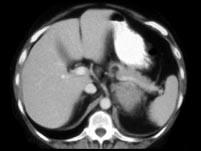

问题 女,47岁,满月脸、向心性肥胖伴高血压1月,请结合所提供图像,作出诊断 ( )

选项 A、左肾上腺嗜铬细胞瘤 B、左肾上腺增生 C、左肾上腺腺癌 D、左肾上腺转移瘤 E、左肾上腺腺瘤

答案 C